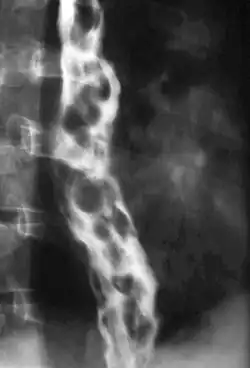

Dilated submucosal veins are the most prominent histologic feature of esophageal varices. The expansion of the submucosa leads to elevation of the mucosa above the surrounding tissue, which is apparent during endoscopy and is a key diagnostic feature. Evidence of recent variceal hemorrhage includes necrosis and ulceration of the mucosa. Evidence of past variceal hemorrhage includes inflammation and venous thrombosis.

Therapeutic endoscopy is considered the mainstay of urgent treatment. The two main therapeutic approaches are variceal ligation (banding) and sclerotherapy.

In cases of refractory bleeding, balloon tamponade with a Sengstaken–Blakemore tube may be necessary, or the use of a fully-covered esophageal self-expandable metallic stent, usually as a bridge to further endoscopy or treatment of the underlying cause of bleeding (i.e.: portal hypertension). Esophageal devascularization operations such as the Sugiura procedure can also be used to stop complicated bleeding. Methods of treating the portal hypertension include: transjugular intrahepatic portosystemic shunt (TIPS), distal splenorenal shunt procedure, or liver transplantation.